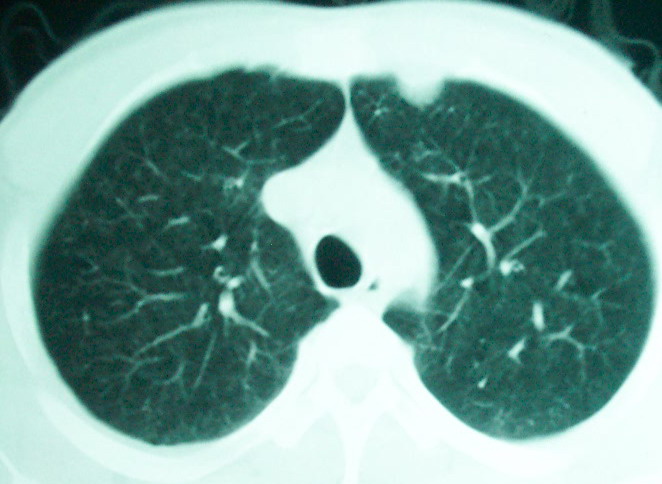

m      37y      发热   咳脓痰月余      ct肺脓肿但住院抗炎治疗后双肺内结节不知该如何解释

治疗后见左肺下野病灶较前缩小但双肺内结节影似无变化请较各位老师该如何下结论    治疗前wbc14.5 治疗后wbc 11.0

结合临床发热,咳痰考虑为血源性肺脓肿,不过双肺结节又在肺的边缘,还是小心一点,抗炎后复查吧

我看是不是可以两元化来解释,左肺下叶还是肺脓疡,而其余病灶考虑肺癌伴肺内转移,我看右肺上叶尖段病灶可见明显毛刺改变为原发病灶.

左下肺病灶除了明显的厚壁空洞 气液平外,明显见壁结节,另两肺多发小结节,综合考虑:左下肺周围性肺癌伴肺内转移.

除了肺内多发结节和左肺下叶的浓疡病灶,还应注意满肺散在的小结节影,还有右上肺前段支气管内膜不光整这些细节,结合病史,肺内多发结节应考虑结核性肉芽!